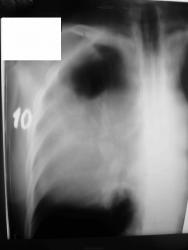

Мужчина 36 лет, рентгеногафия и КТ грудной полости.

Жалобы на субфебрильную температуру, боли в грудной клетке справа, слабость, похудание. ФГ 10 месяцев назад - норма.

Снимки от 18.08.09

Интенсивное, однородное затемнение в средних отделах справа, слева норма - мною был заподозрен м/долевой плеврит, пациент был направлен в областной центр торакальной хирургии. Затем онкодиспансер, затем институт рака в Киеве. Результат гистологии тератобластома средостения. 2 курса химиотерапии контрольное КТ в октябре - отрицательная динамика.

Огромное объемное образование, мне кажется, исходит из средостения. Может, лимфома?

Массивное неоднородное мягкотканное новообразование, исходящее из верхней или средней трети переднего средостения, оттесняет крупные сосуды вправо и кзади. По локализации должна быть злокачественная тимома. Хотя и лимфому наверное, не стоит отбрасывать, Ходжкинская маловероятна.